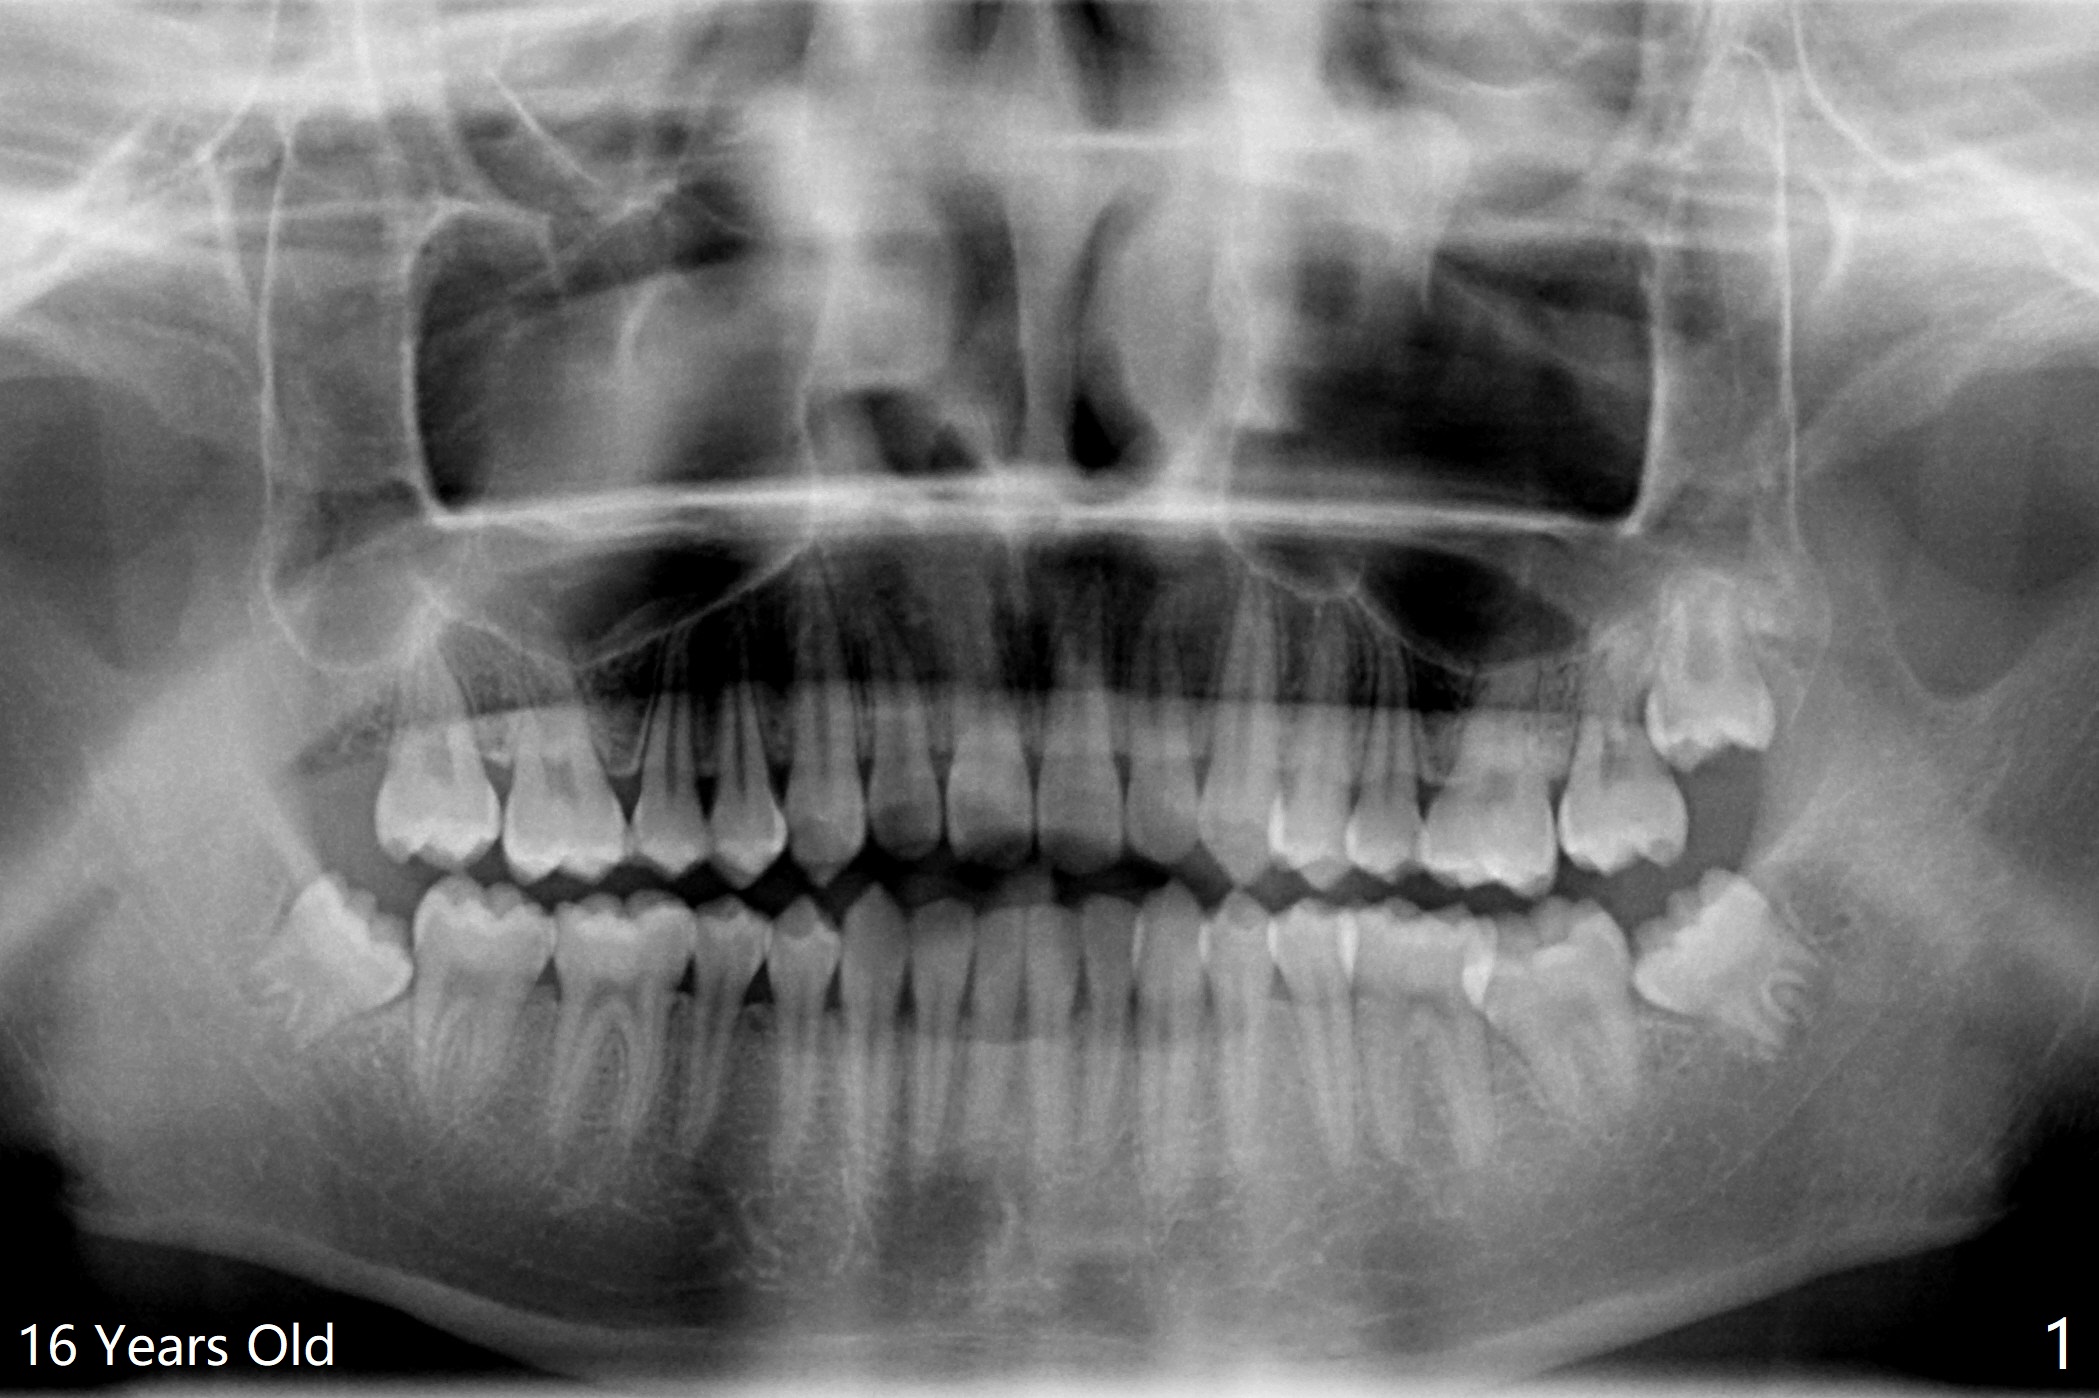

A 20-year-old man has been our patient irregularly since the age of 13. His mother reported that he did not brush well, probably related to gag reflex. Panoramus is taken at the ages of 16 and 20 (Fig.1,2). In fact a primitive cyst forms (Fig.1) before calcification of the impacted upper right 3rd molar (dentigerous cyst, Fig.2). After extraction and enucleation of the cyst, Augma will be injected into the cavitation, followed by Osteogen plug.